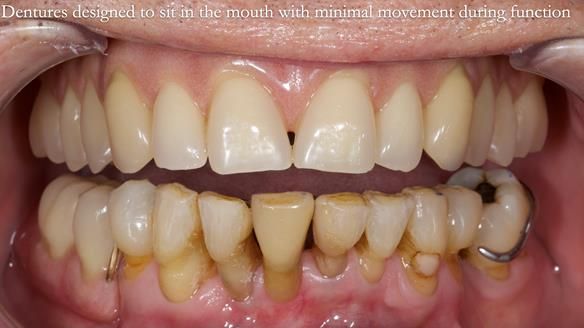

Welcome to my Newsletter 54 showing the making and fitting of dentures (a complete upper metal reinforced denture, a lower immediate partial denture and a definitive Scandinavian designed, metal based lower partial denture) for David, a 75 -year-old man. The full protocol workflow is presented including the use of dentate photographs to mimic his natural teeth.

“Straight even teeth”

“White in colour”

“Well fitted and comfortable”

Interestingly we found that the upper complete denture when finished and fitted didn’t have good enough retention for David’s satisfaction. It was relined by adding compound to the buccal flanges – to almost overextend into the sulcus to ‘create’ a sulcus, followed by using a light bodied silicone impression material. This improved the function of the C/-considerably. A lower Scandinavian hygienically designed lower RPD was also provided which helped with occlusal stability and reseating the upper denture – further improving the fit.